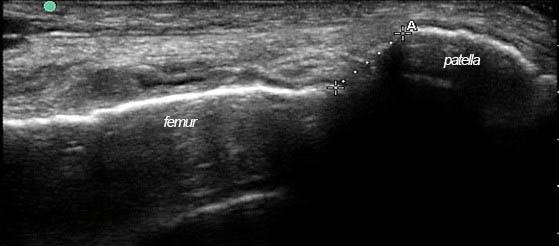

Nine soft-fixed cadavers were used in this study. The cadavers had been donated for anatomical examination and research under the Human Tissue Act (2004). The distance between the lateral femoral condyle and the lateral edge of the patella were measured by B-mode real-time ultrasound, and then by direct measurement, in two positions, neutral and at 20° hip adduction.

本研究使用了9具软固定尸体。这些尸体是根据《人体组织法》(2004年)捐赠用于解剖检查和研究的。在中立位和髋关节内收20°这两个位置,通过B型实时超声测量股骨外侧髁与髌骨外侧边缘之间的距离,然后进行直接测量。